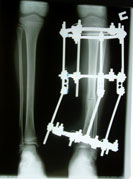

А на вопрос мужа, так почему так всё произошло? Он спокойно ответил:такое бывает. Муж опять: кто виноват-врачи, я хочу призвать их к ответственности. А Онипко: никто, так сложился случай. Это бывает редко, но встречается. У Вас глубокий косой перелом, учитывая что девочка у Вас гиперактивная, при нагрузке и ходьбе в гипсе смещение могло произойти. Но если произошло, значит кто то виноват. А муж искал знакомых адвокатов, чтобы наказать. Онипко ещё раз повторил: врачи здесь не причём и показал пальцем вверх-всё от всевышнего и многие вещи от нас не зависит. Защищая своих врачей, а он там работал 13 лет зав.отделением, убеждал нас, что может произойти само исправление с возрастом. Но на наш вопрос: Вы убеждены на 100%, долго думая со вздохом, если честно на 100-нет. И начал философствовать, что даже советский аэрофлот не даёт гарантию. У меня создалось впечатление, что у них у врачей, особенно которые работали вместе и долгие годы знали друг друга будут оправдывать, защищать и т.д. Так что нам делать? Думайте. Мы с мужем не спали ровно двое суток. На 3-й день пришли и сказали, оперируйте. И что и как это будет, объясните. "Учитывая что ребёнок через тоненькие спицы прокольчики, без швов, слегка послабив уже сросшуюся неправильно б/б кость устранив создавшуюся укорочение, скрученость кости и подвывих м/б. Уверен, что Ваш ребёнок уже через неделю будет бегать в аппарате." Поверили, потому что от него исходила такая уверенность!!! На следующий день сдали анализы и 13 июля нас прооперировали. Всё получилось на что мы надеялись, дочка на 2-й стала ходить на костылях наступая на прооперированную ножку. На 5-й день начались манипуляции с аппаратом, она вообще никак на них не реагировала и с каждым днём была всё активнее. Когда забывали напомнить ей про костыли, она ходила без них смешно прихрамывая. После рентгеновского снимка в четверг, Н.Н. ей ещё что то подкрутил и отправил нас домой в г. Иртышск. Заходила гл.медсестра, перевязочная и подробно объяснили, как делать перевязки. Убедили что всё пройдёт спокойно,а если уж 1 на 1000, то срочно на вертолёте и на площадку клиники (шучу). У нас наконец то наступило успокоение и уверенность, что всё будет хорошо. Всем спасибо.

16 августа аппарат снят без наркоза. Сделали ей детское обезболивающее внутримышечно. Похныкала чуть-чуть. После снятия бегает и прыгает! Свободно может стоять на одной ноге, с которой только что сняли аппарат. Ножки одинаковые и ровные. Всем кто принимал участие в лечении моей дочери, огромное родительское СПАСИБО!